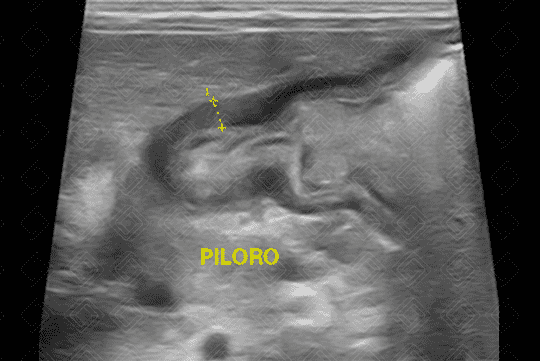

Texto alternativo para a imagem Figura 3. Créditos: Dra. Elazir Mota - Rio de Janeiro/RJ

Descrição das figuras 2 e 3: Ultrassonografia do abdome de lactente com 27 dias de vida evidenciando muscular do piloro espessado (sua muscular media 4 mm) e o canal pilórico alongado. Observe a aparência em alvo do piloro no seu corte transversal, outro sinal clássico de EHP (seta vermelha).